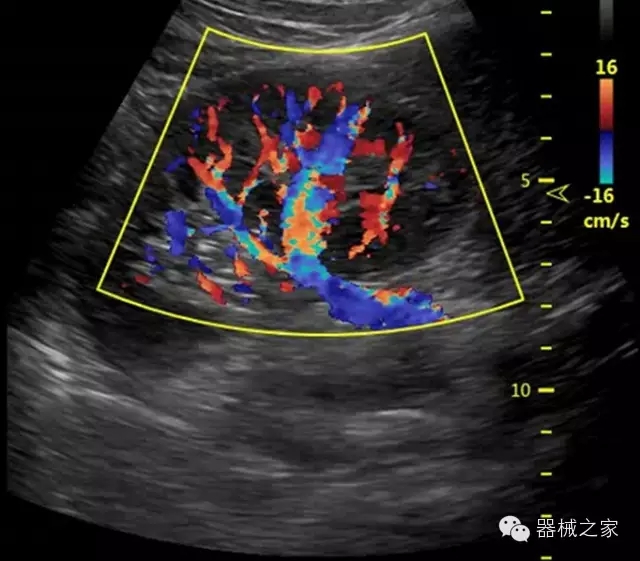

臨床圖片賞析

·獨(dú)有的HoloTM PW 實(shí)時(shí)3取樣門(mén)PW成像技術(shù),精確進(jìn)行血管診斷;

·一鍵優(yōu)化B、Color、PW,Auto Doppler自動(dòng)識(shí)別血管位置、偏轉(zhuǎn)角度等,提高工作效率;

·智能微血流成像技術(shù):智能微血流捕捉技術(shù)可以提取出隱藏在背景噪聲中的弱血流信號(hào),大大提高低速血流的敏感性;